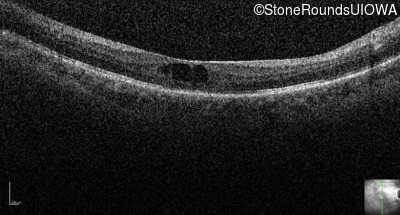

Optical Coherence Tomography - Right - 20/50 +2

Exemplar / OCT Stack

Optical Coherence Tomography - Left - 20/160